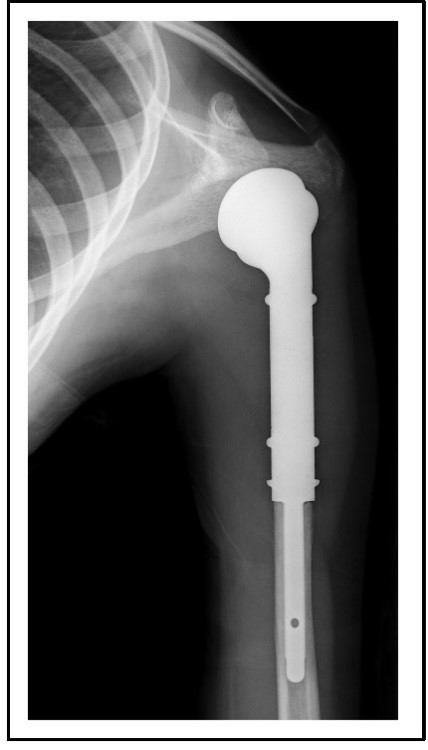

Abb. links: Röntgenbild eines Ewing-Sarkoms in einem Humerus (Oberarmknochen).

Abb. rechts: Schemazeichnung.

Abb.: Durch die vollständige Entfernung eines Tumors mit dem entsprechenden Sicherheitsabstand zum gesunden Gewebe konnte das Schultergelenk nicht erhalten werden. Daher wurde dieses durch eine spezielle Tumorendoprothese rekonstruiert, die wieder eine gute Funktionalität der Schulter gewährleistet.